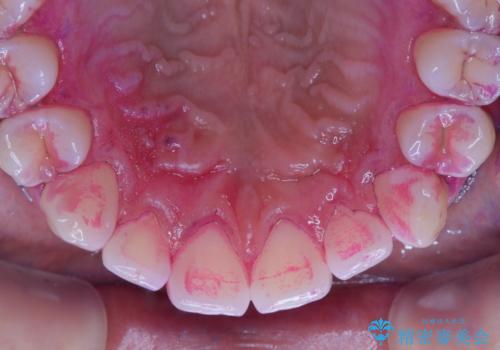

染め出しをして磨き残しのチェックと歯のクリーニング

染め出し液を使ってプラークを染め出すことにより、普段の歯みがきで磨き残している場所を目で確かめることができます。